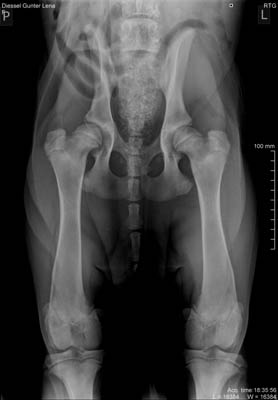

Unsere Doggenhündin "Indra" hat die veterinärmedizinischen

Untersuchungen (HD, ED, Herzultraschall) und die Zuchtzulassungsprüfung (ZZL) erfolgreich bestanden.

| - Seit 7 Generationen keine Feststellung von HD in der Mutterlinie. (HD A oder B) |

| - Seit 7 Generationen keine Anpaarung von Rüden mit leichter Hüftgelenksdysplasie (HD C). |

| - Seit 3 Generation Kontrolle auf Ellenbogengelenksdysplasie. |